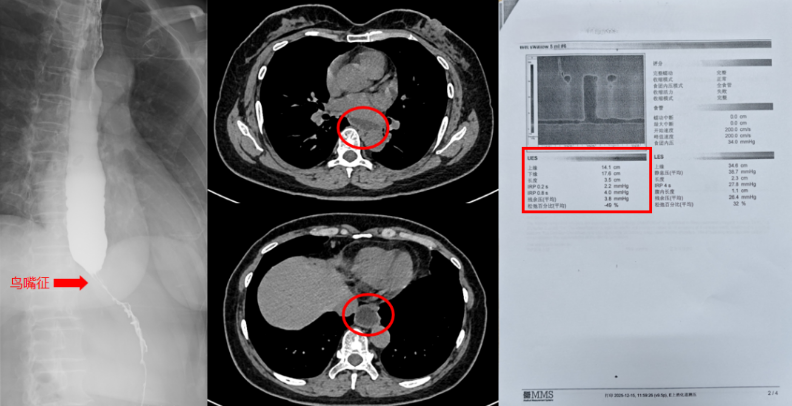

经过详细检查,王阿姨被确诊为罕见的贲门失弛缓症Ⅱ型。这是一种原发性食管动力障碍性疾病,发病率较低,临床症状易与胃食管反流病、食管肿瘤等常见病混淆,确诊难度较大。其核心病理问题在于食管下括约肌松弛不全、食管体部蠕动消失,导致食物无法顺利通过贲门进入胃内,形成“梗阻-潴留-反流”的恶性循环,患者常伴随进行性吞咽困难、体重下降等症状,严重时还会引发吸入性肺炎、营养不良等并发症。

针对王阿姨的病情,胸科病院胸部疾病诊疗中心张潍教授团队高度重视,结合她的病情严重程度、身体状况,量身定制了“胸腔镜下Heller肌切开术联合胃底折叠术”的微创治疗方案。该手术虽技术难度较高,但能在解除食管梗阻的同时,建立有效的抗反流屏障,长期疗效稳定,是治疗此类复杂病例的优选方案。

术后,护理团队遵循加速康复外科路径,为王阿姨启动个性化康复计划,从疼痛管理、营养支持到呼吸功能训练进行全流程精细化管理。术后造影结果显示,王阿姨的贲门梗阻已完全解除,术后48小时便能正常进食,困扰她一年多的进食难题终于得到根治。